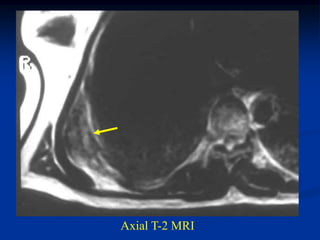

Case #1171

9 year male with desmoid tumor posterior axilla

tumor

CT scan

Axial T-2 MRI